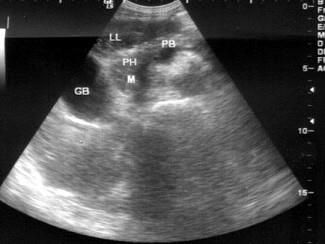

问题 患者女48岁,上腹部疼痛不适3个月,皮肤巩膜黄染1个月余。B超检查如图所示,根据超声声像图诊断为?(?)

选项 A.胆总管下段癌 B.壶腹部癌 C.胰头癌 D.腹主动脉旁肿大淋巴结 E.结肠癌

答案 C